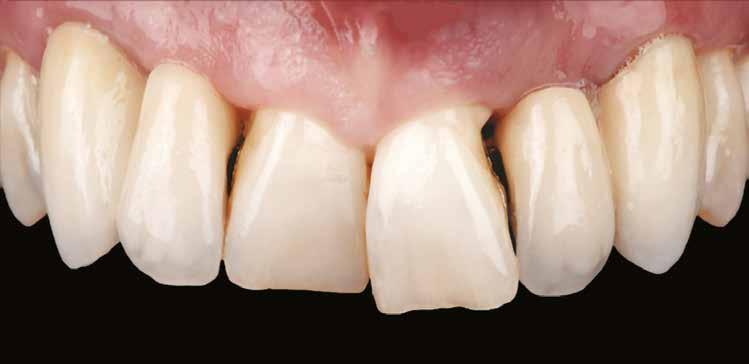

Kiindulási helyzet

A páciens egy 56 éves nőbeteg, nem dohányzik, általános egészségi állapota jó (ASA I), gyógyszert nem szed, ismert allergiája nincs. Fő panasza, amellyel klinikánkat felkereste, hogy elégedetlen mosolyával. Elmondása alapján az utóbbi években krónikus gyulladás alakult ki frontfogai körül, amely érezhető mobilitáshoz vezetett. Ez a probléma jelentősen befolyásolta a magabiztos beszédben és étkezésben. A páciens hosszú távú megoldást keresett, de aggódott a kezelések alatt fellépő esetleges fájdalom miatt. Az extraorális vizsgálat során megállapítottuk, hogy a mosolyvonal közepesen magas és a frontfogak torlódottak (1–2. ábrák). A szájüregi vizsgálat során a 1.2, 2.1 és 2.2 fogak körül előrehaladott parodontális tapadásveszteséget és mobilitást találtunk (3. ábra). A CBCT (cone beam CT) felvételen látszott, hogy a 2.1 fog bukkális csontfala hiányzik (4. ábra).

1. ábra: Az extraorális vizsgálat közepesen magas mosolyvonalat mutatott.

2. ábra: A torlódott felső frontfogak.

3. ábra: Az intraorális vizsgálat során a bal felső nagymetszőnél és mindkét oldali kismetszőnél parodontális tapadásvesztést és mobilitást találtunk.